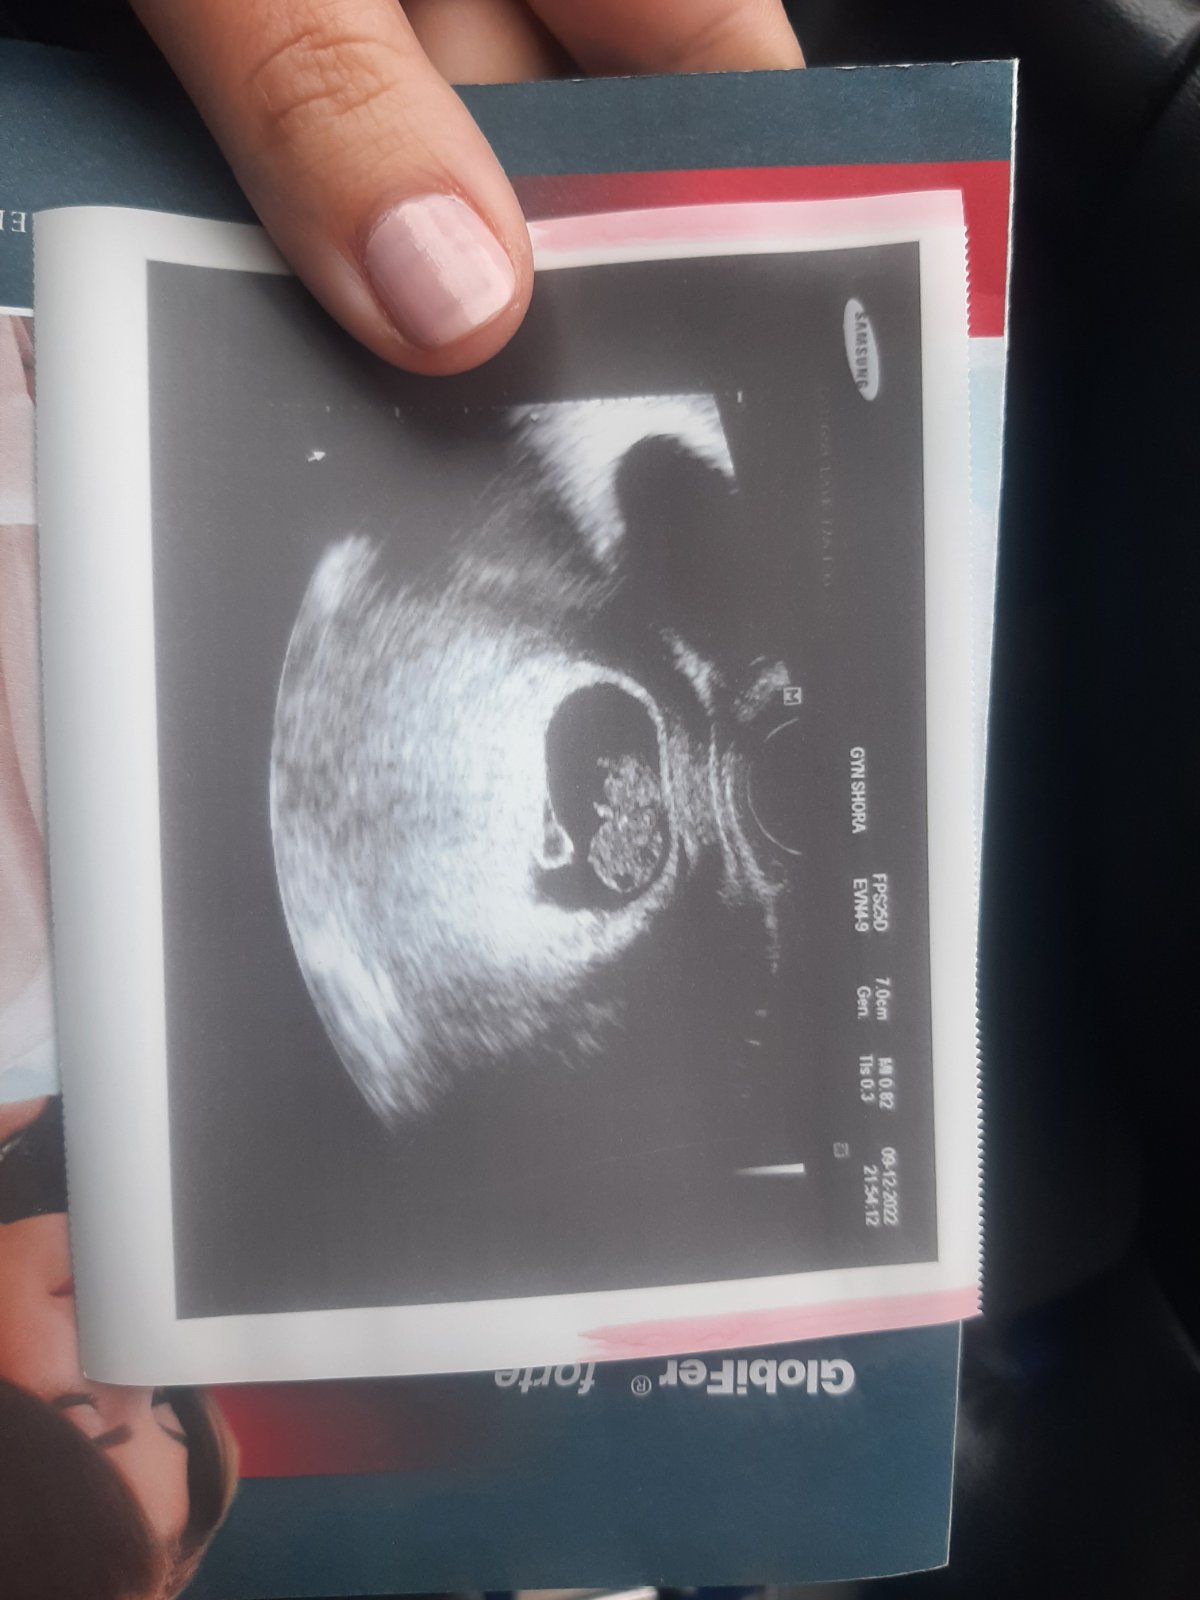

@kristynaprandl jinak dnes jsem byla na kontrole. dle utz jsme 9+0, malý má 3,2cm a příští týden se mám objednat na genetiku na odběry a screening 🥰🥰

Ahoj holky jedu od dr. ráno jsem měla velky křeče v břiše tak jsme radši jeli a chvála bohu je mímo v pořádku, podle UTZ 9+4tt srdicko bije krásně🥰

@kristynaprandl jeee koukam,ze máme i podobnou fotečku ve stejný tyden🥰

@kristynaprandl když jsem byla 15.11. tak byl/a o deset dní menší než mělo být 🙈 ale teď to prý dohnal/a a odpovídá týdnu 🙏🙏